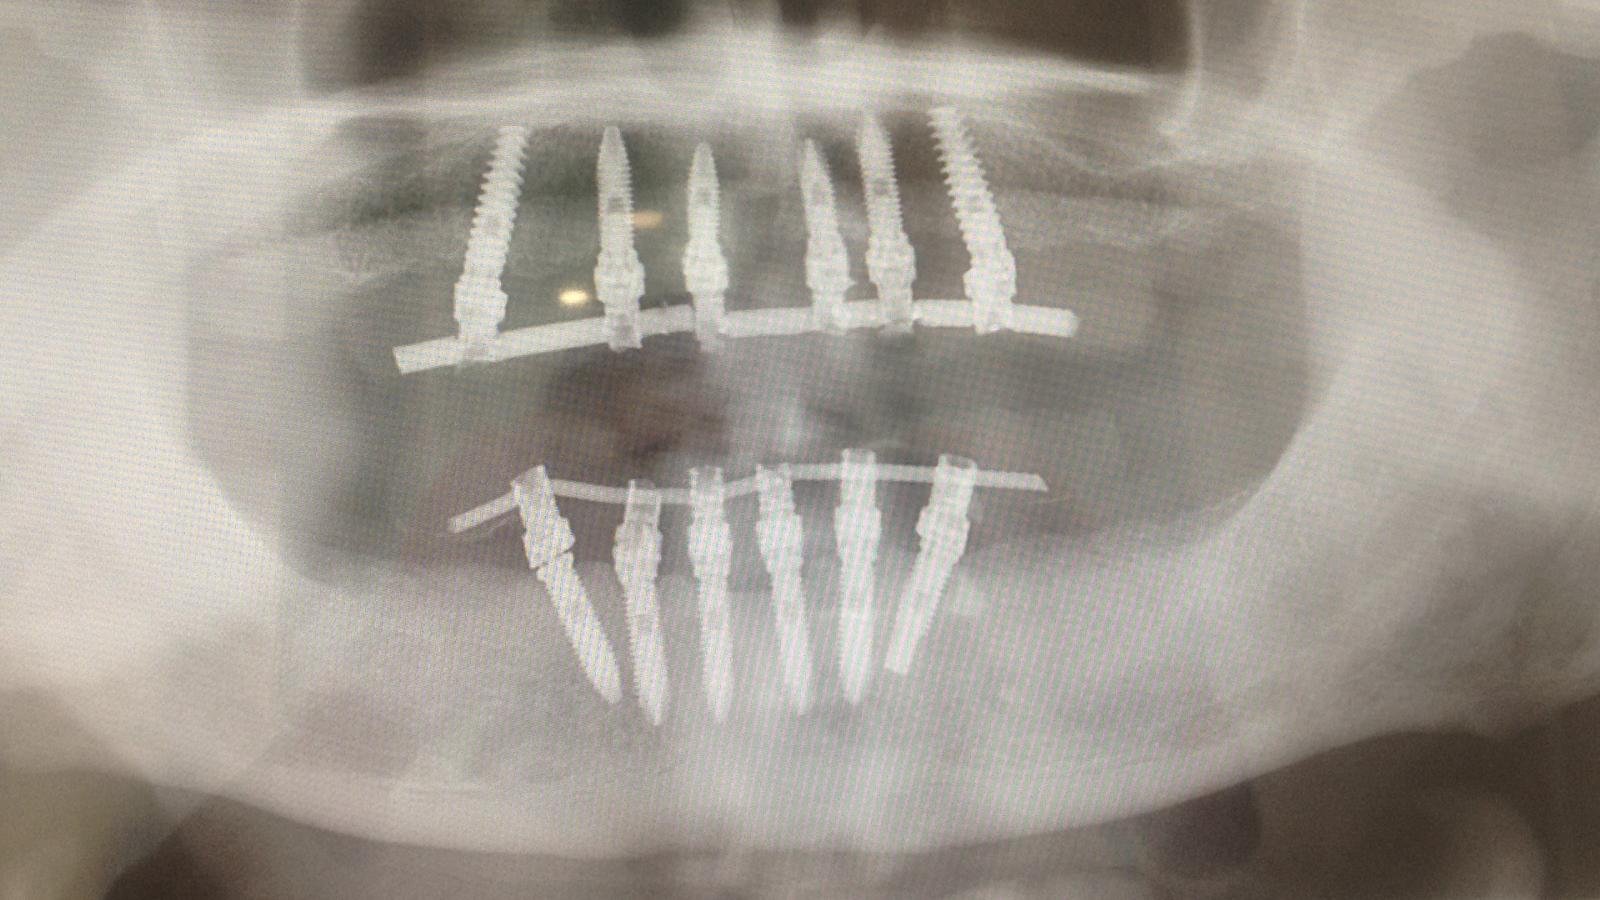

Paciente acude tras la colocación de un implante postextración hace mas de un año en una clínica a la cual no quiere volver por referir una mala experiencia. Tras la [...]